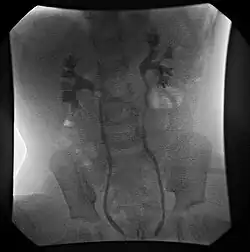

- Fluoroscopic voiding cystourethrogram (VCUG)

VCUG is the method of choice for grading and initial workup, while RNC is preferred for subsequent evaluations as there is less exposure to radiation. A high index of suspicion should be attached to any case where a child presents with a urinary tract infection, and anatomical causes should be excluded. A VCUG and abdominal ultrasound should be performed in these cases